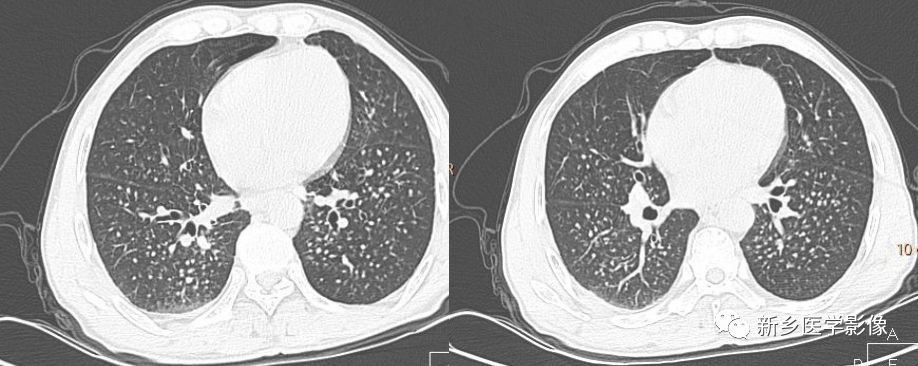

CT

小结节,直径2-5mm,边缘清楚或不清楚,小叶中心性和胸膜下

网状影不明显

弥漫分布,以上叶和后部为主

融合团块,形态不规则,含坏死区

局灶性小叶中心性肺气肿

不规则型或瘢痕型肺气肿

淋巴结肿大和钙化